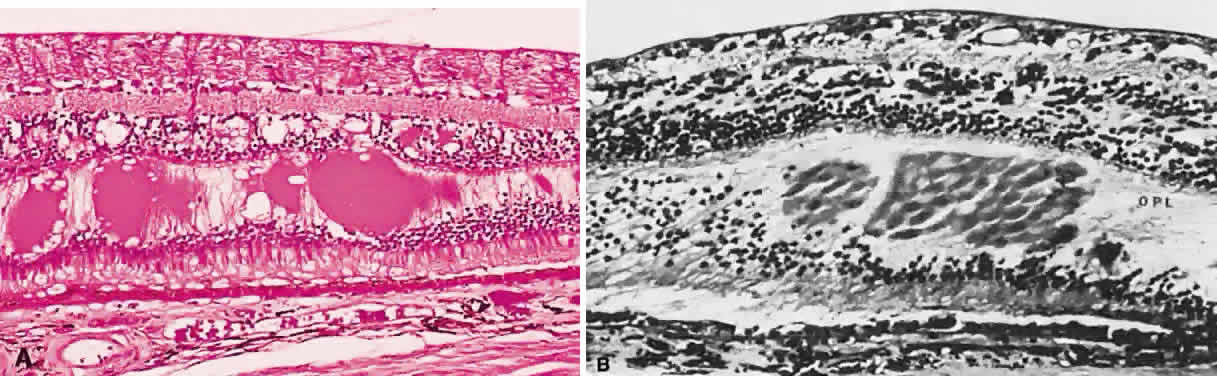

Typical cystoid degeneration involves the formation of cyst-like spaces at the level of the outer plexiform layer (Blessig-Iwanoff cysts) (Fig. 59). These are common lesions, present in most persons from the first decade of life. These “cysts” appear to become more numerous with age. Coalescence of these cysts may result in “senile” retinoschisis.23 Reticular cystoid degeneration involves a disruption at the level of the nerve fiber layer. It is located frequently just posterior to the area of typical cystoid degeneration. A network of fine, branching blood vessels is seen commonly over the surface of reticular cystoid degeneration.

Fig. 59. A. Typical cystoid degeneration of the peripheral retina with cyst-like spaces in the outer plexiform layer (Blessig-Iwanoff cysts). These cysts sometimes coalesce, and the inner layer breaks down to form a hole. B. Peripheral cystoid degeneration with atrophic holes. (A, courtesy of Ralph C. Eagle Jr, MD, Philadelphia, PA. B, courtesy of William Tasman, MD, Philadelphia, PA).